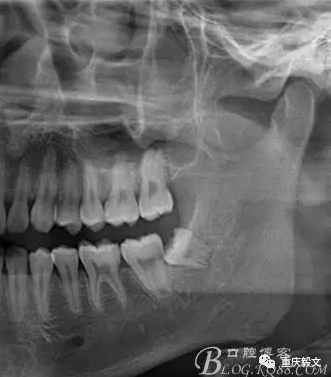

患者、于xx、男、26歲。主訴:左側(cè)下后牙牙齦腫痛不適數(shù)天。??茩z查:38未萌出,可探及牙冠。x光:低位近中,牙冠抵住37牙頸部。診斷:低位近中阻生。處理:建議拔除38.患者同意治療方案,簽知情同意書。

圖1 術(shù)前的影像檢查 : x線檢查的目的:檢查有無智齒的存在。如有阻生智齒存在,確定是部分骨阻生還是完全骨阻生。檢查阻生智齒的類型,是近中位、垂直位或水平位等。檢查阻生智齒的大小和牙根的長短、數(shù)目、形態(tài)等;有無牙根彎曲和彎曲方向與程度;牙根有無肥大、是否與周圍骨質(zhì)粘連。.檢查阻生智齒與第二磨牙的關(guān)系.檢查阻生智齒與下頜管的關(guān)系及距離.